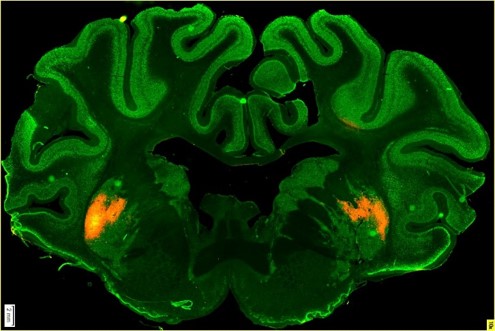

Kolega Štefan Juhás aplikoval virus s fluorescenčním proteinem prasátkům do mozku, konkrétně do oblasti striata v bazálních gangliích, která jsou odpovědná za koordinaci pohybu. Pak jsme prasata utratili a pozorovali mozkové řezy, abychom viděli, kam všude se virus se značkou rozšířil. Rozšířil se velmi dobře, aniž by došlo k poškození buněk, jenom k mírnému zánětu vlivem fluorescenční značky.